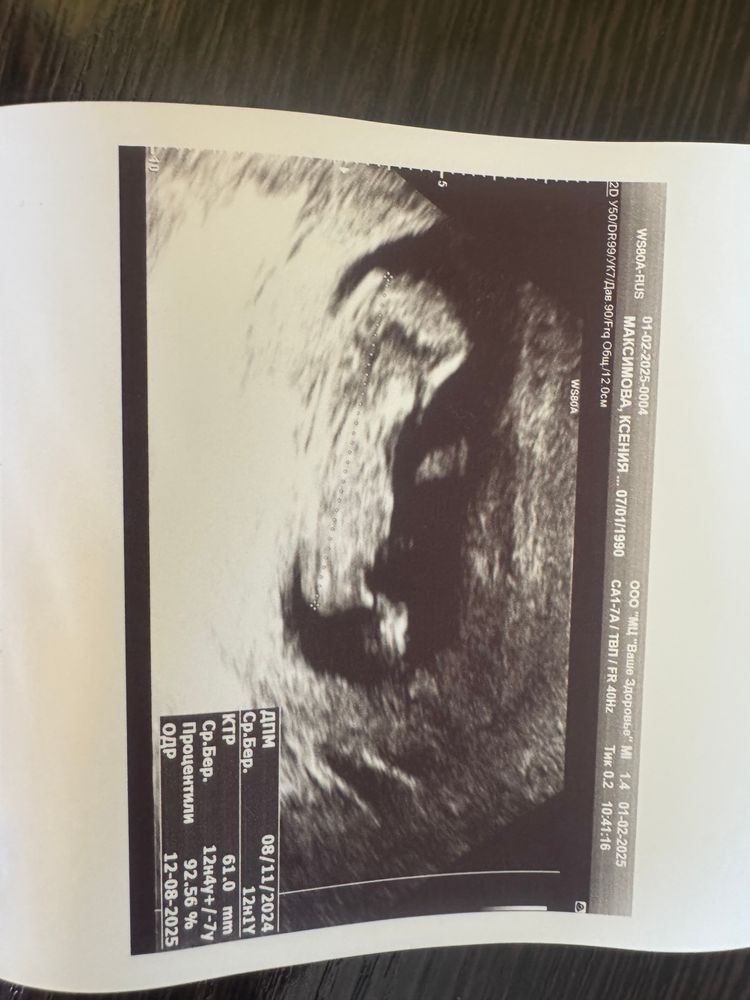

Ксения

Ксения, в РД еще не была, мне поздно назначили скрининг, по узи уже почти 15 недель будет (( вот и пошла платно . Это «ваше здоровье» на античном